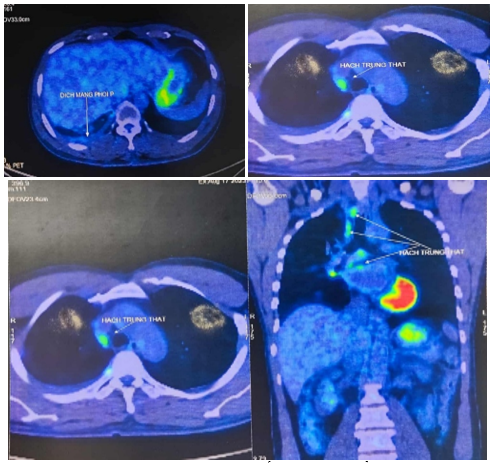

Bệnh nhân được chụp PET/CT tại Bệnh viện Vinmec cho kết quả: Các nốt đặc rải rác thùy giữa và dưới phổi phải, các nốt lớn tăng chuyển hoá FDG (suvmax 3,6), ít dịch màng phổi dày 9mm, nhiều nốt rải rác màng phổi thành ngực, hạch nhóm 2R,4R/7 rốn phổi phải, hạch lớn KT 17x10mm.

Hình 3: Hình ảnh chụp PET/CT các nốt tổn thương u tại phổi phải (mũi tên đỏ), nốt di căn màng phổi phải (mũi tên vàng)

Hình 4: Hình ảnh chụp PET/CT: Hạch trung thất, dịch màng phổi phải (mũi tên chỉ)